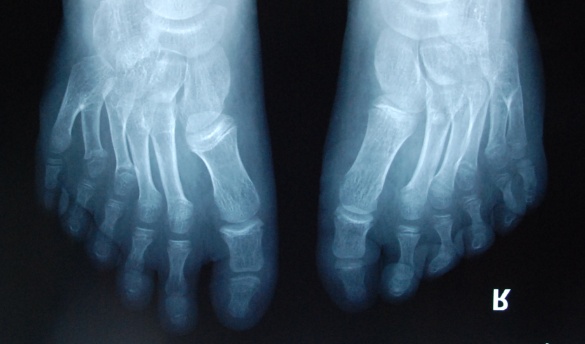

廈門(mén)眼科中心小兒眼科修陽(yáng)暉博士在日常的診療過(guò)程中就接診了不少這樣的的特殊家庭,讓其尤為印象深刻的就是一年前接診的BBS綜合征患者。當(dāng)時(shí)來(lái)院就診的是一對(duì)親兄弟,之前已在多家醫(yī)院做過(guò)檢查,因其均有較大散光和斜視,肉眼下眼底檢查未見(jiàn)異常,故外院均診斷為弱視,這也符合眼科門(mén)診常規(guī)的診斷邏輯與思維。但由于兄弟倆均有智力發(fā)育遲緩、特殊面容及四肢均有六指和六趾的特異體征引起了修陽(yáng)暉博士的警覺(jué):會(huì)不會(huì)是一種特殊遺傳性疾病或綜合征?后續(xù)的檢查結(jié)果進(jìn)一步證實(shí)了修陽(yáng)暉博士的懷疑---患兒均有夜盲,ERG、VEP及OCT檢查顯示雙眼的視網(wǎng)膜神經(jīng)上皮層結(jié)構(gòu)及功能均明顯異常。由于之前未遇到此種病例,修陽(yáng)暉博士在診斷一欄寫(xiě)下視網(wǎng)膜色素變性并打上了個(gè)問(wèn)號(hào),同時(shí)留下了病人的聯(lián)系方式。

BBS綜合征(Bardet-Biedl綜合征)是一種主要累及纖毛結(jié)構(gòu)與功能的罕見(jiàn)常染色體隱性遺傳性疾病。纖毛分布于哺乳動(dòng)物體內(nèi)的大多數(shù)細(xì)胞,它是一種廣泛存在于各種細(xì)胞表面的細(xì)胞器,體型微小但結(jié)構(gòu)復(fù)雜、作用強(qiáng)大,能感知細(xì)胞外機(jī)械和化學(xué)信號(hào)變化并協(xié)助其轉(zhuǎn)導(dǎo)到細(xì)胞內(nèi)部從而引起細(xì)胞應(yīng)答。高等動(dòng)物的視覺(jué)、觸覺(jué)、嗅覺(jué)、聽(tīng)覺(jué)的傳遞都依賴(lài)于體內(nèi)外正常的纖毛結(jié)構(gòu)和功能。因此BBS綜合征常累及全身多個(gè)系統(tǒng)和器官,在臨床上主要表現(xiàn)為:視網(wǎng)膜色素變性、智力發(fā)育異常、向心性肥胖、多指(趾)、性腺發(fā)育異常、腎臟異常。除此之外還有許多諸如:語(yǔ)言發(fā)育障礙、聽(tīng)力異常、嗅覺(jué)異常、斜視、白內(nèi)障、散光、牙齒發(fā)育異常、短指(趾)、并指(趾)、肝纖維化、糖尿病、高血壓等表現(xiàn)。